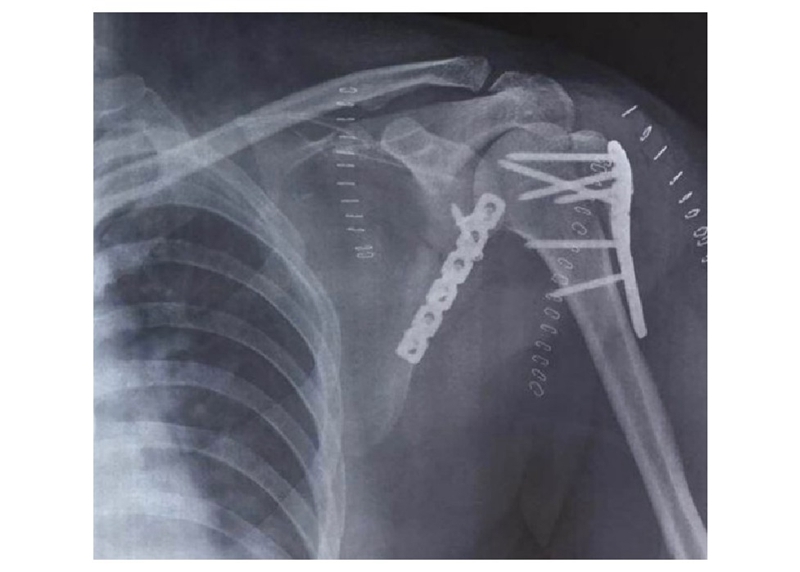

病例5(图23)为患者因车祸导致肩胛骨及肱骨近端骨折,肩胛骨体部骨折块移位显著。

图23 CT三维重建示肱骨近端骨折,肩胛颈及肩胛骨体部骨折

本例患者在术中对肩胛骨体部骨折块采用缝线辅助固定技术,将高强度缝线穿过骨折线两侧预钻孔后,以Nice结进行固定。肱骨近端及肩胛颈内下方骨折采用接骨板固定(图24)。

术后X线显示接骨板位置良好,实现肩胛骨骨折解剖复位(图25)。

图25 X线示肱骨近端及肩胛骨内固定位置良好,骨折复位满意